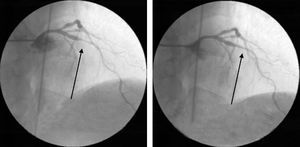

During the latest hospitalization, invasive coronary angiography was repeated, which once again revealed coronary findings that could easily have been interpreted as new lesions, but these resolved after aggressive treatment with intracoronary nitrates (Fig. 6).

Coronary revascularization (whether percutaneous or surgical) is not indicated in cases of isolated coronary spasm without fixed coronary stenosis.2 Our patient's coronary anatomy was reassessed during subsequent admissions, with due caution in the light of what had occurred during the first hospitalization, and with generous doses of intracoronary nitrates in order to establish a differential diagnosis between isolated vasospasm (which was in fact confirmed) and obstructive atherosclerotic disease.